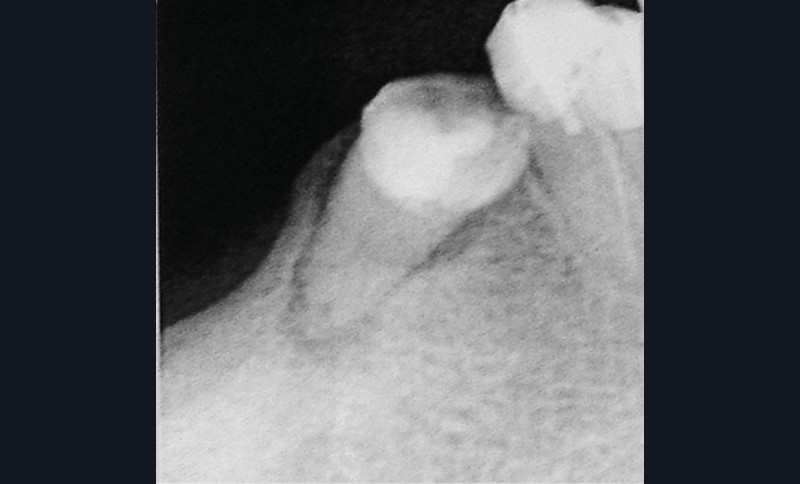

Si les recommandations et les différents auteurs s’accordent depuis longtemps pour contre-indiquer la pose d’implant dans le contexte malin, celle-ci n’est pas contre-indiquée chez un patient traité par IRO dans un contexte bénin [9]. De nombreuses publications ont montré des taux de succès comparables à ceux de la population générale. Cependant, ces données sont à considérer avec discernement car le recul et le niveau de preuve scientifique sont encore faibles [10]. Ainsi, il semble raisonnable de ne pas réfuter de principe la solution implantaire chez ces patients. Mais il conviendra de les informer clairement du rapport bénéfice/risque. Trois points semblent indispensables pour aider à la décision. Il s’agira d’évaluer la durée du traitement (plus ou moins 3 années), les facteurs de comorbidité (diabète, corticothérapie notamment) et l’invasivité du geste chirurgical (implant unitaire ou multiple, nombre de sextants concernés) (fig. 3). Dans tous les cas, les alternatives thérapeutiques devront être proposées et discutées avec le patient.